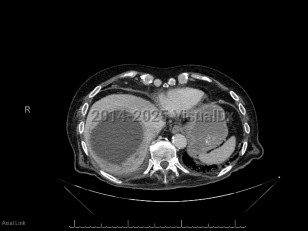

Imaging Studies image of Pyogenic liver abscess - imageId=6828400. Click to open in gallery.  caption: '<span>Axial CT image demonstrates a  large thick-walled fluid collection at the hepatic dome with mildly  enhancing peripheral rim, consistent with liver abscess.</span>'

Axial CT image demonstrates a large thick-walled fluid collection at the hepatic dome with mildly enhancing peripheral rim, consistent with liver abscess.